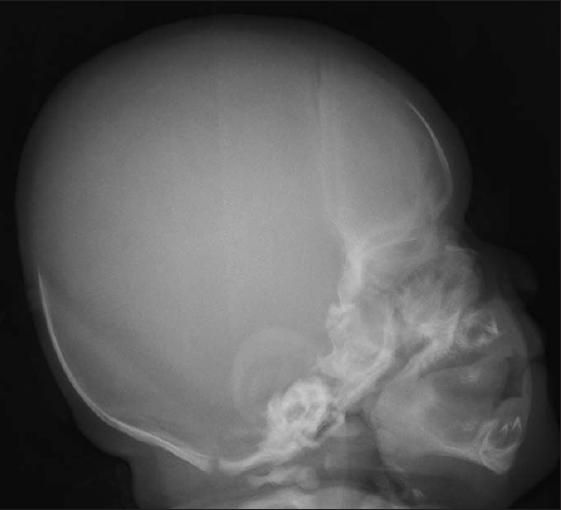

The distinctive facial features of Apert syndrome are acrocephaly (or oxycephaly) with bicoronal synostosis, maxillary hypoplasia, and high-arched palate (Figure 1). Cleft palate occurs in one-third of patients.9 The cranial malformations typically cause strabismus and hypertelorism. Patients may have malformations of the corpus callosum and limbic structures with ventriculomegaly that leads to hydrocephalus. 10 Hearing impairment can result from persistent middle ear effusion or congenital ossicular chain fixation.11 Airway obstruction secondary to palatal defects is common12; in this case, it may have contributed to the patient's desaturation event.

Figure

Acrocephaly with bicoronal synostosis, maxillaryhypoplasia, and high-arched palate are characteristic of Apertsyndrome.

A skeletal survey revealed sclerosis in the region of the coronal sutures that confirmed synostosis (Figure 3). Radiographs of the hands demonstrated soft tissue symphalangism with abnormally broad and fused proximal phalanges; several distal phalanges were absent (Figure 4). Radiographs of the feet demonstrated bifid proximal first metatarsals and some hypoplastic proximal phalanges (Figure 5). The infant had a normal spine, 12 paired ribs, and a normal shoulder girdle and pelvis. The long bones of the upper and lower extremities were symmetrical and normally formed.

Sclerosis in the region of the coronal sutures, consistent with synostosis, isnoted in this radiograph of the skull.